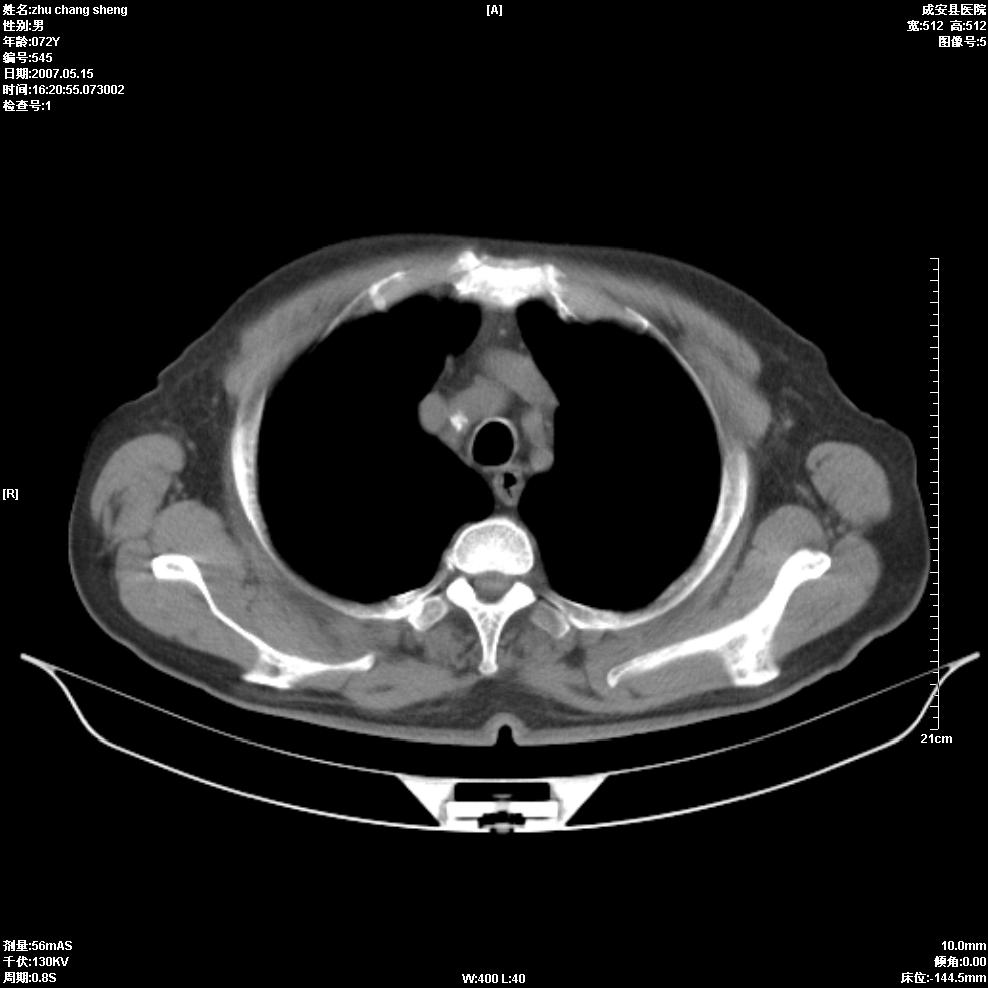

以下是引用医博云天在2007-5-15 19:10:00的发言:[br]心包积液,胸腔积液,心影增大,左心为主。

以下是引用zhangzhongshou在2007-5-15 20:21:00的发言:[br]心包积液可以肯定有,肿块显示不清,建议增强或mri检查。

以下是引用jinning在2007-5-15 21:06:00的发言:[br]心包积液可以肯定,建议增强或mri检查吧!

以下是引用拾荒者在2007-5-15 22:28:00的发言:[br]心包膜增厚,有少量积液,右室前壁示均匀软组织密度影,边界欠清,建议增强扫描或mri检查与室壁瘤鉴别。

以下是引用还珠格格在2007-5-19 9:50:00的发言:[br]病人与5月18日 做了核磁增强扫描 确诊为前上纵隔侵袭性胸腺瘤。